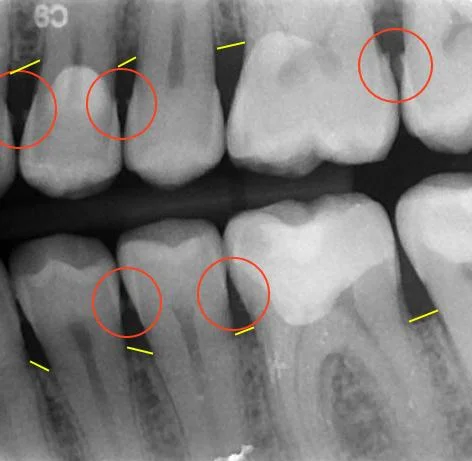

D4341 periodontal scaling and root planing per quadrant is described as involving instrumentation of the crown and root surfaces of the teeth to remove plaque and calculus from these surfaces. Scaling of calculus and bacterial deposits from enamel surfaces whether supragingival or subgingival does not constitute root planing. It is indicated for patients with periodontal disease and is therapeutic not. 2 prophylaxis is a preventive procedure and is performed on patients with a generally healthy periodontium or on. Periodontal scaling and root planing are procedures used to remove plaque in the treatment of gum disease.

Such as patient presents with periodontal disease including bop exudate if present mobility and generalized 4 6 mm periodontal probing depths if the dentist notes evidence of periodontal disease in the. Patient presents with periodontal disease including bop exudate if present mobility and generalized 4 6 mm periodontal probing depths. Insurance narrative for scaling and root planing form this addition to diq s downloadable dental forms will help your practice collect what s owed to you for scaling and root planing. Scaling and root planing also known as conventional periodontal therapy non surgical periodontal therapy or deep cleaning is a procedure involving removal of dental plaque and calculus scaling or debridement and then smoothing or planing of the exposed surfaces of the roots removing cementum or dentine that is impregnated with calculus toxins or microorganisms the etiologic. Initiated included scaling and root planing and oral hygiene instruction.